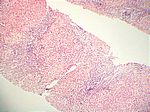

Aktive aggressive chronische Hepatitis, HE